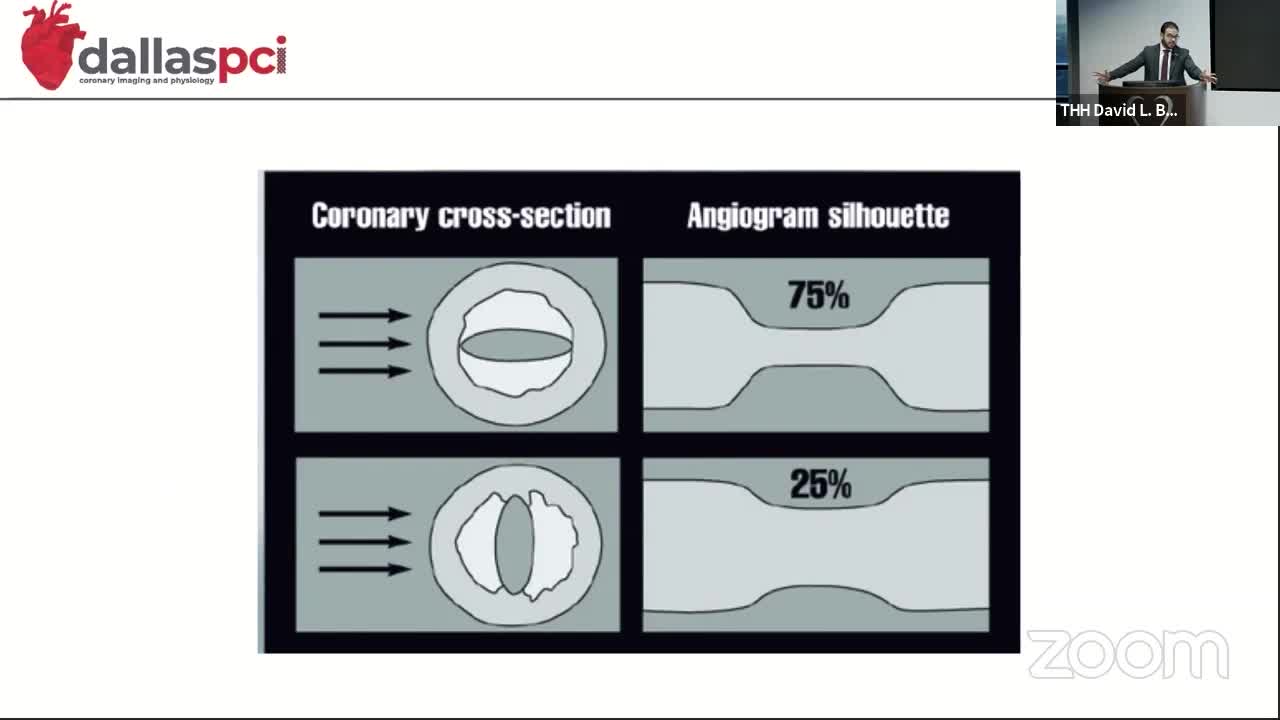

Our mission is to provide a collaborative environment and educational opportunities for physicians, scientists, nurses, and medical professionals to discuss and teach advanced techniques, improve clinical knowledge, and enhance the ability to provide excellent patient care, which ultimately improves patient health outcomes. To that end, the education program has strived to meet this goal educating and training the local, regional, and national medical community on the most recent advancements in medical science and research.